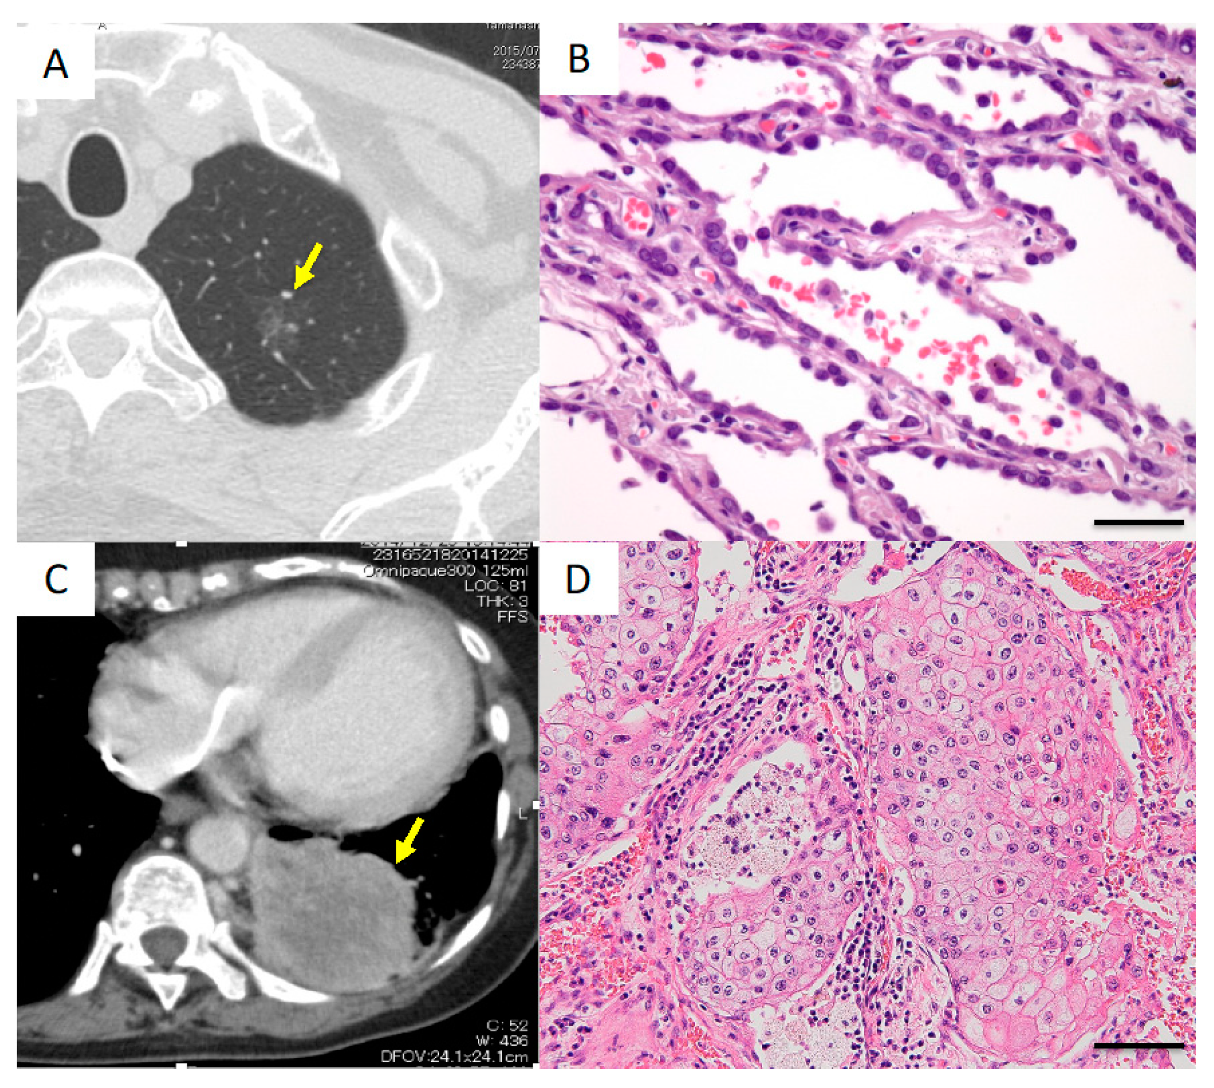

Case I

A 72-year-old man underwent left upper division segmentectomy because a ground-glass neoplasm was found in the left upper lobe (Figure 4A). The lesion was pathologically diagnosed as adenocarcinoma in situ (AIS), TisN0M0, stage 0 (Figure 4B). AIS is a well-differentiated adenocarcinoma, and the survival rate after resection is reportedly 100% [8]. Three indels in the noncoding region of the SFTPB gene were detected (Table 2). The detection of noncoding indels in a case of such early, well-differentiated lung cancer suggested that noncoding indel mutations occur in the early phase of tumor evolution.

Figure 4.

Radiological and histological findings in Cases I and II. (A,B) Case I. (A) Computed tomography (CT) image showing a ground-glass neoplasm in the apical portion of the left lung. The arrow indicates the lesion. (B) Histologically, the tumor was diagnosed as adenocarcinoma in situ. Scale bar, 20 μm. (C,D) Case II. (C) CT image showing a large mass lesion in the left lower lobe. The arrow indicates the lesion. (D) Histologically, the tumor was diagnosed as squamous cell carcinoma. Scale bar, 40 μm.

Case II

A 79-year-old woman was found to have a massive tumor measuring 90 mm in diameter in the left lower lobe and underwent left lower lobectomy combined with resection of the thoracic wall and diaphragm (Figure 4C). Histologically, the lesion was diagnosed as squamous cell carcinoma, pT4N0M0, stage IIIB (Figure 4D). An indel in the noncoding region of the SFTPB gene was detected (Table 2).

Thus, noncoding indels were detected in lesions ranging from early-stage lung cancer, as in case I, to massive and poorly differentiated cancer, as in this case.